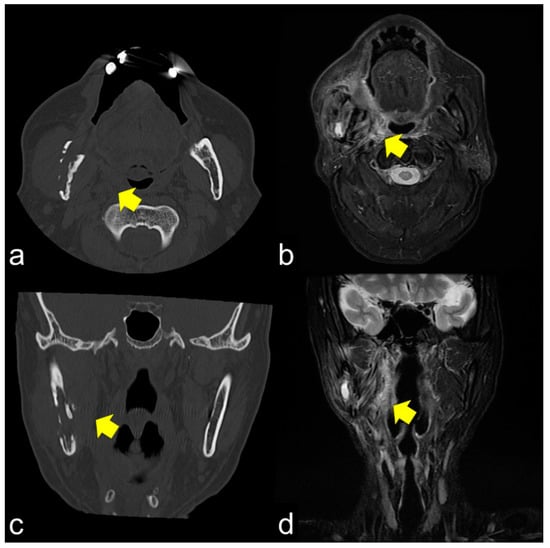

MRI showed that the damage to the bone marrow by RT continued even after the long-term asymptomatic phase. Even if there are no clinical symptoms of ORN, the bone marrow is considered abnormal for a long time after RT. Considering the CT images, the consolidated bone region would have devitalized or reduced vitality, possibly fibrosis with lower blood supply. Partial bone resorption and reactive fibrosis showed a mixed image of bone consolidation (low intensities on T1 WI and heterogeneous hyper-intensities on T2 WI), as Kaneda has previously suggested [13,21]. Moreover, the homogeneous hyper-intensities of T2 WI may be mild bone marrow inflammation considering the clinical symptoms of ORN. From a clinical point of view, tooth extraction within the radiation field should be performed with caution at any time after RT. If abnormal bone marrow is invaded by triggers, the symptoms of ORN would change from the chronic inflammation phase to the acute inflammation phase. Tooth extraction before RT is recommended, but it does not prevent ORN; the essence of ORN is devitalized bone. Considering soft tissue, CT and MRI often show inflammation in the surrounding masticatory muscles, and MRI can confirm the inflammatory symptoms around the masticatory muscles [39]. These symptoms are related to trismus. As the ORN stage progressed, chronic trismus increased, which indicated that inflammation from the bone marrow extended beyond the cortical bone to the inferior border of the mandible and into the surrounding soft tissue. Trismus was observed with cortical disruption on CT (Figure 3a,c) and abnormal T2 signal intensity, enhancement, and thickening of the masseter and pterygoid muscles (Figure 3b,d). In such a condition, antibiotics only cause acute inflammation in the chronic phase. The degree of trismus would improve with surgical resection of the necrotic bone, however, with only conservative treatments, it is unclear whether trismus can be improved.

Figure 3.

(a,b) Axial CT and T2 WI magnetic resonance images show cortical bone disruption and abnormal signal intensity in the masticatory muscle; (c,d) Coronal images also show chronic inflammation, particularly in the medial pterygoid muscle. Chronic inflammation in the masticatory muscles results in trismus.